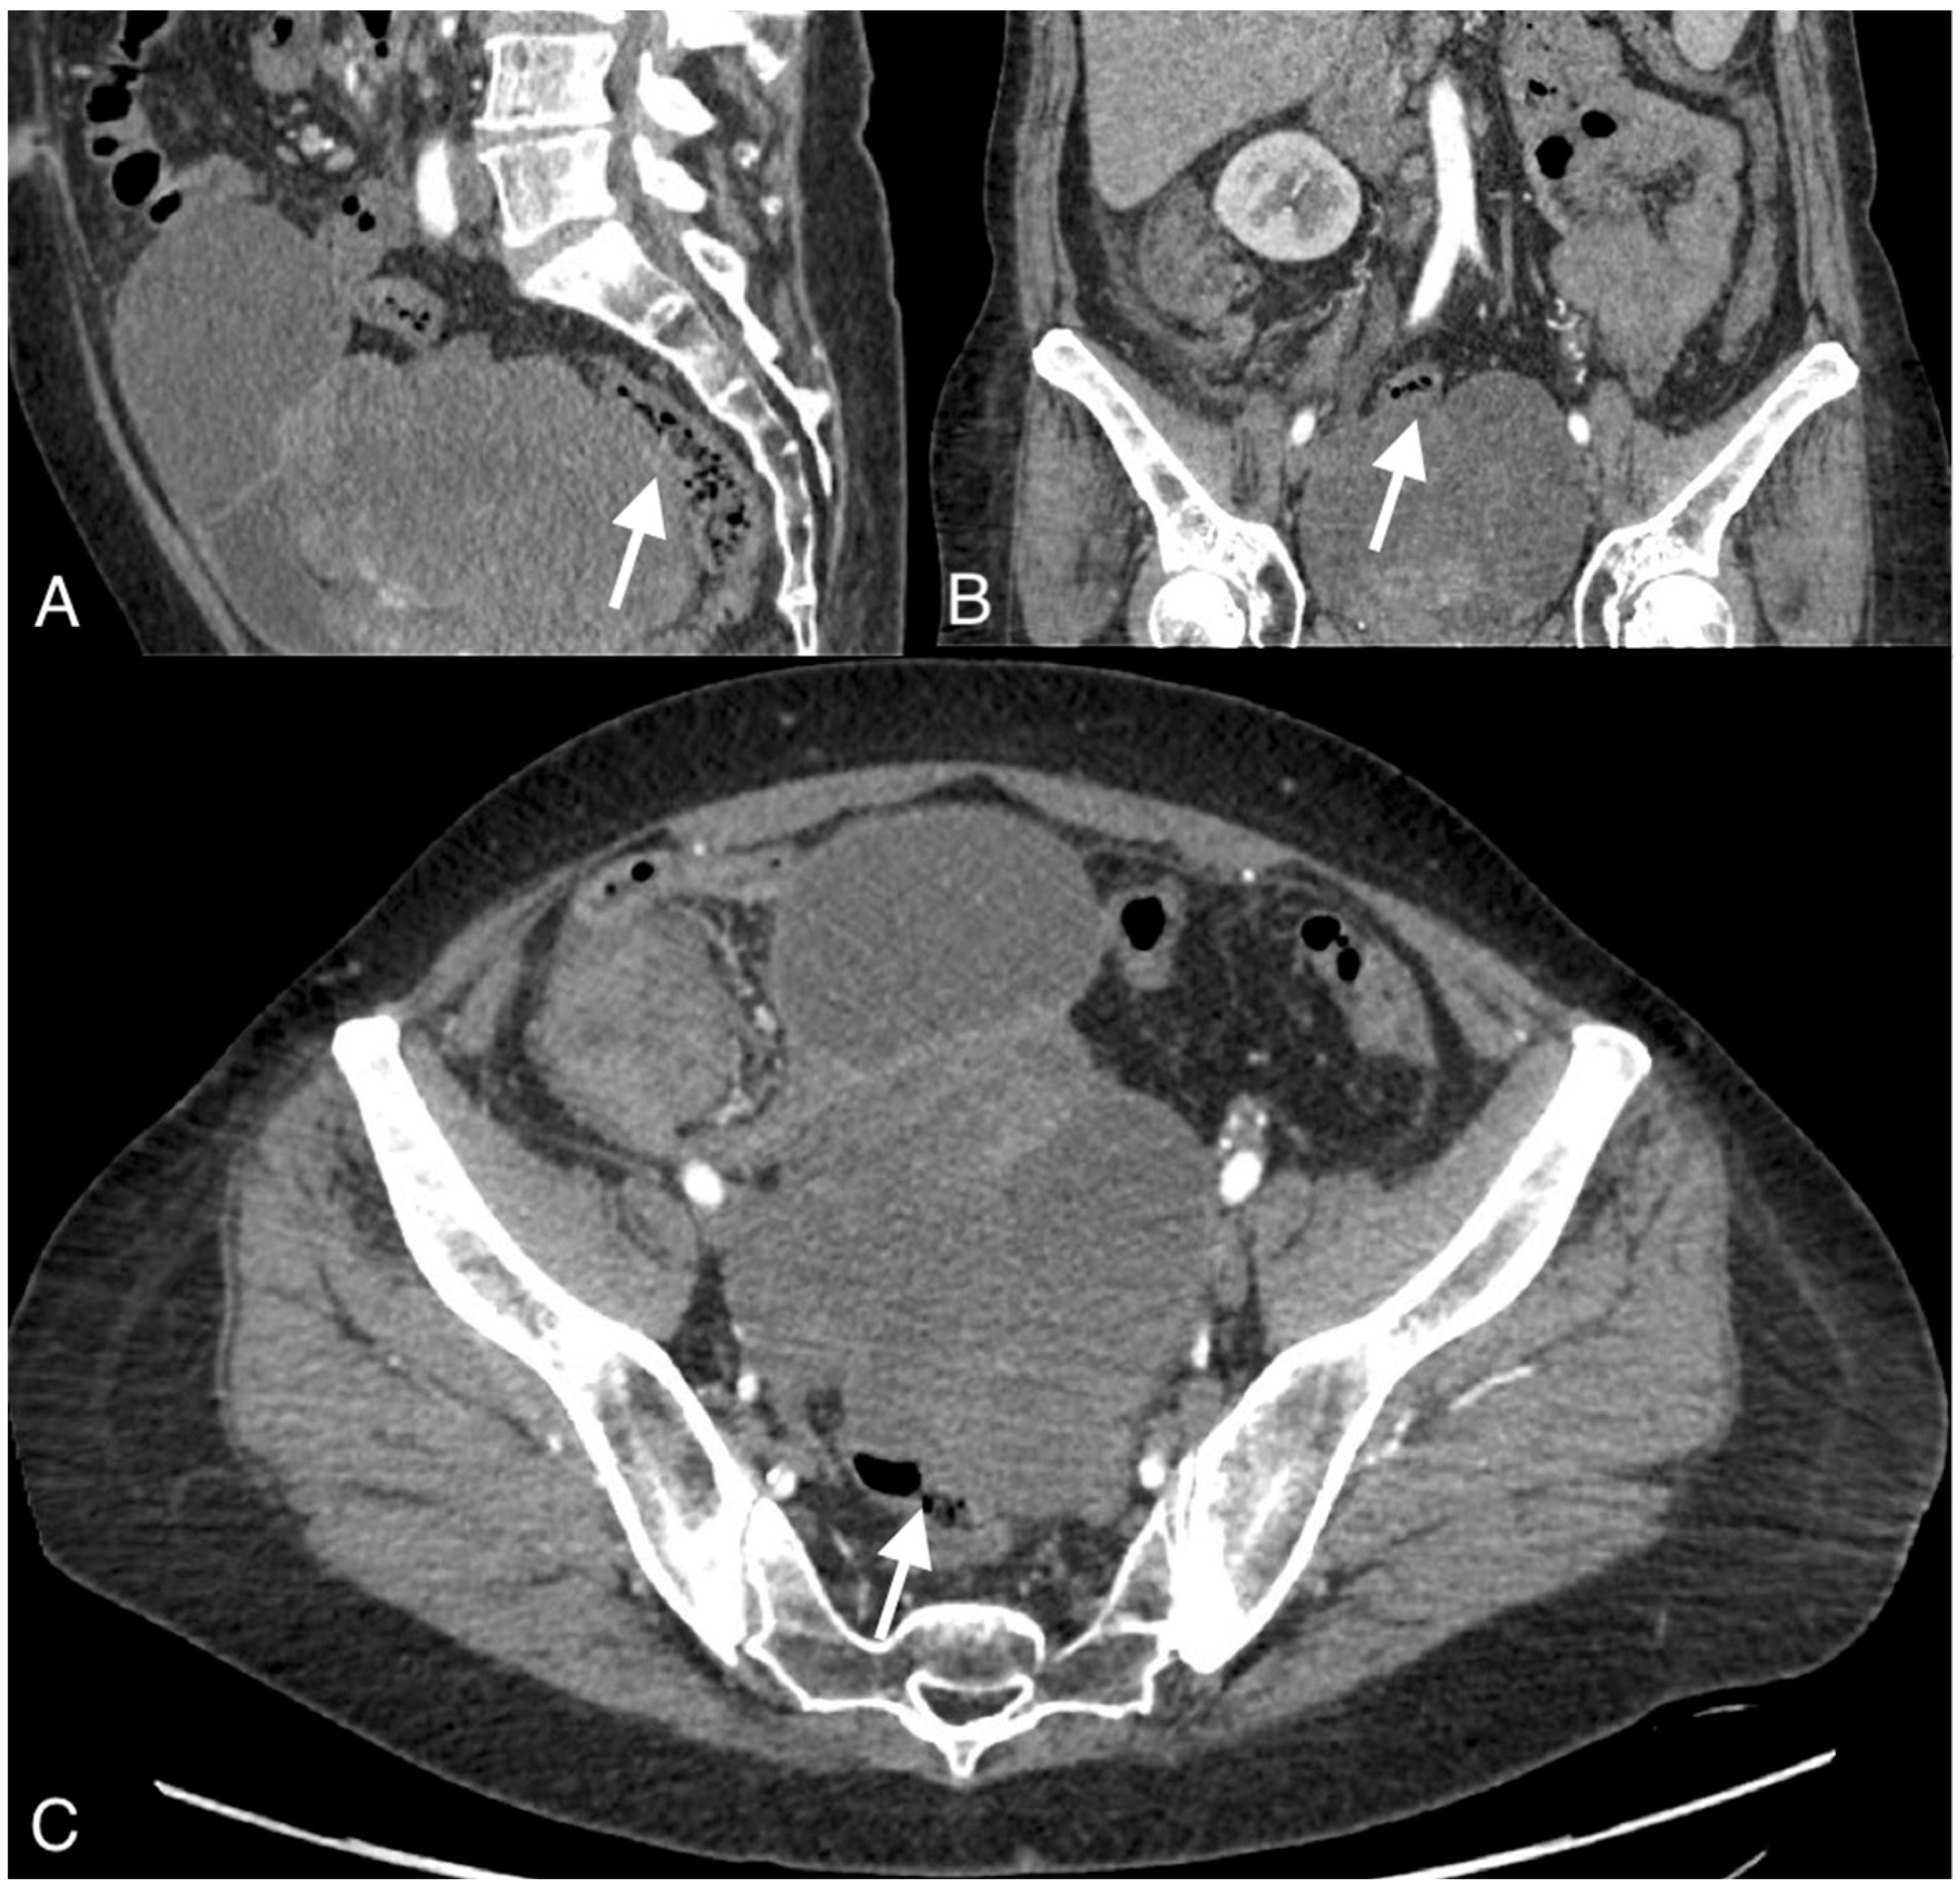

Figure 4.

Images of a 37-year-old woman with a recurrent tumor of high-grade serous ovarian cancer with fistula between tumor and sigmoid colon. MRI T2-weighted images obtained in axial plane (A), coronal plane (B), and T1 post-contrast (C) show a large solid/cystic tumor and the fistula (arrows) between tumor and sigmoid colon. DWI (b1200) shows restricted diffusion in the tumor but not in the fistula (D).

To confirm the suspected fistula, the patients were referred for MRI. In all cases, the fistula was visible on the MR images, showing hypointensity on the T2 and T1 post-contrast sequences but no restricted diffusion on the DWI sequence. The fistula in one of the patients was hyperintense on T2 images and hypointense on T1-weighted images and showed restricted diffusion on DWI.

Interobserver agreement was 75% for CT and 87.5% for MRI, corresponding to a high level of agreement (Figure 4 and Figure 5).